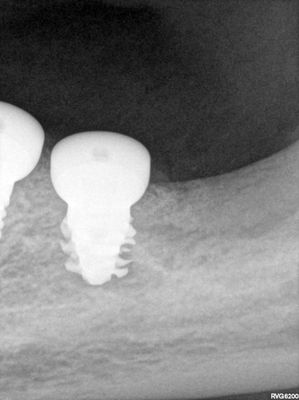

large amount of bone loss at time of exo 36/37 done 2 months ago. Good healing of bone except for small socket area at 36 region. buccal bone lower than palatal about 1mm, decided to place tissue level implants opposed to grafting, gaining back height is unlikely, difficult access case with large tongue. Implants placed with 36 about 1.5mm buccal exposed, 37, .5mm mesial exposed, healing abutments palced grafted all sites with sticky bone followed by collagen membrane soaked in prf fluid, 2 holes cut for implants. additonal fibrin membrance placed on buccal prior to suturing.